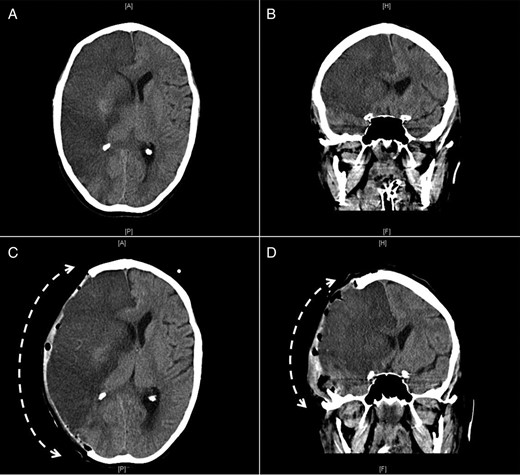

On further examination, her legs were cold and mottled and a CT angiography of the abdomen, pelvis and both lower extremities revealed occlusion of the distal infra-renal abdominal aorta and iliacs (Fig. 2A and B) and superficial femoral arteries with weak runoff on the left and no runoff on the right side (Fig. 2C and D). Multifocal infarcts of the spleen and both kidneys were also noticed (Fig. 2A).

Sagittal (A) and coronal (B) computed tomographic angiogram images of the abdomen and pelvis and coronal images (C and D) of both lower extremities showing occlusion of the distal infra-renal abdominal aorta (thin arrow) and iliacs (thick arrows) and superficial femoral arteries with weak runoff on the left and no runoff on the right side (angled arrows) with multifocal infarcts of the spleen (S) and left kidney (K).